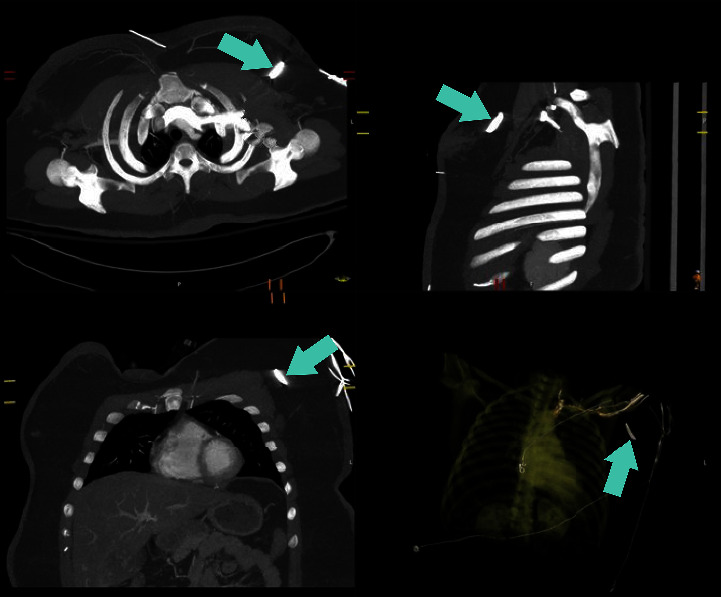

Background: Unintentionally retained foreign bodies in the breast are a rare phenomenon. Most reported cases are iatrogenically derived from surgeries and procedures. Only a handful of reported cases refer to noniatrogenic causes, including bullets, a sewing needle, and a headscarf pin. However, there are no reports to date that describe a retained foreign body in the breast after a motor vehicle collision or a similar traumatic event or from a decorative steering wheel emblem decal. Case Description: We report the case of a 25-year-old female who was involved in a motor vehicle collision with airbag deployment that led to a left breast retained foreign body, a steering wheel emblem decal. On presentation to the emergency room, she reported left chest pain associated with a puncture wound lateral to the left nipple. Imaging at that time was consistent with a metallic object embedded in the subcutaneous tissue of the left breast. Four months after the accident, the patient continued having daily burning pain in the associated area. As such, surgical excision was recommended, and wire-localized excision of the foreign body was subsequently performed. Grossly, the foreign body appeared as a metallic object with rhinestones, which the patient confirmed was a decorative emblem decal that was on her steering wheel. The postoperative course was uncomplicated, and follow-up examinations revealed resolution of the left breast pain. Conclusions: This case underscores a unique presentation after a common accident-a retained foreign body in the breast after a motor vehicle collision-and its successful surgical intervention leading to a favorable postoperative course. Notably, the National Highway Traffic Safety Administration recently advised drivers against adding decorative emblem decals to their steering wheels for this reason. The case therefore highlights safety precautions that should be taken regarding the addition of this type of accessory.

Abstract Image